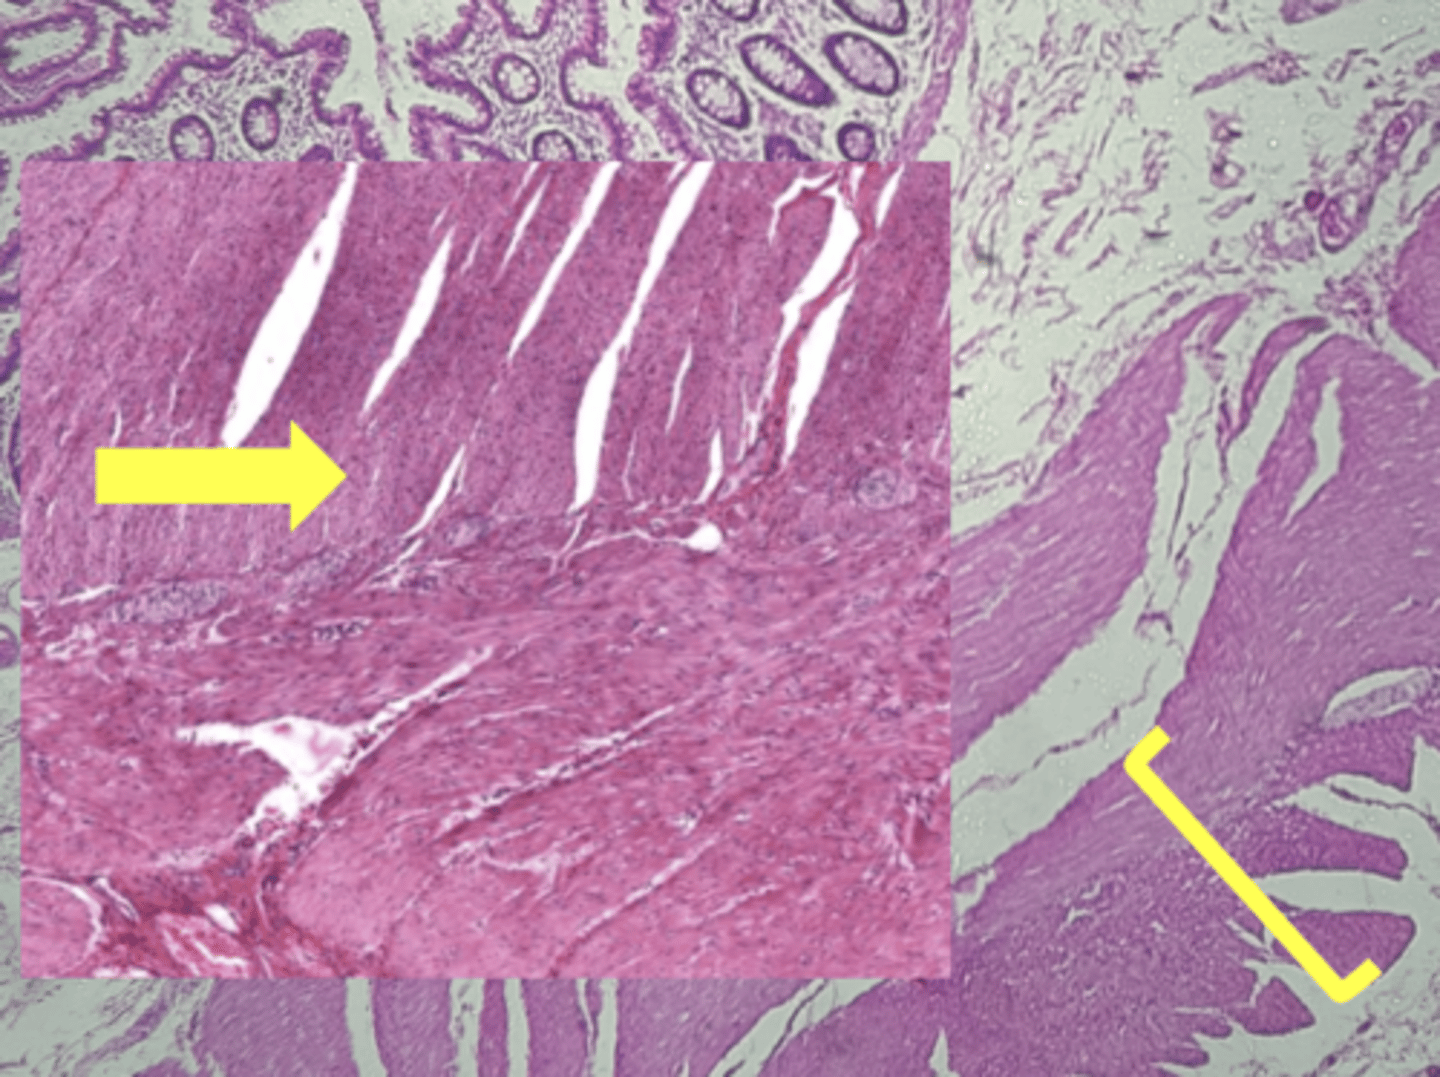

stomach

name the tissue

muscularis externa (3 LAYERS-KEY CHARACTERISTIC)

(stomach)

oblique layer

circular layer

longitudinal layer